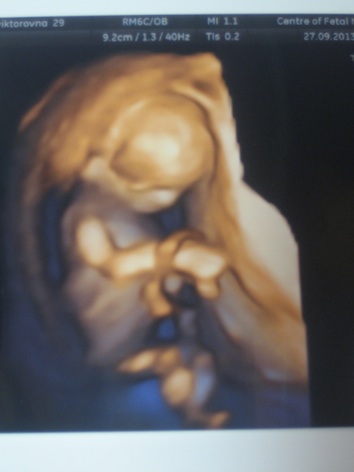

Ну что, Центром медицины плода на Ваське и врачом Порозовой Еленой Николаевной я, то есть мы с мужем, полностью довольны - все на высшем уровне, даже 3д и 4д показали, хотя я не запрашивала - видимо это в комплекте. И подвигались, и поспали за сеанс, и ручкой помахали, показав все пальчики, и мозг у нас бабочкой, и носовые косточки есть, и ТВП 1,5мм, в 3Д видны (скорее врачу, чем нам - опытный глаз видимо надо иметь, чтобы разобраться) правильные черты личика ;)